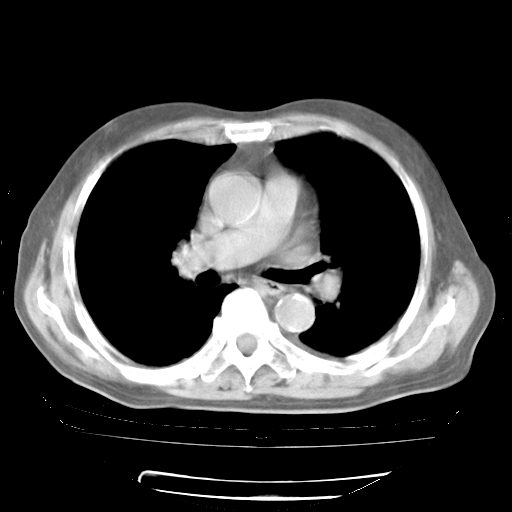

4月28日肺部CT——再次出现类似去年5月9日——透光度降低,“间质性”改变。

个人阅读4.14日肺部CT平扫:纵隔窗无异常,但肺窗示:双下肺内、后基底段有片絮状侵润影,部位以后基底段为著,以间质改变为主,呈急性肺泡炎征像,和首次住院影像学有相似之处。仅是个人读片,明日请相关专家再读片哈。其它建议同上。

1、108#的是4月14日的胸部CT(发此贴时还没看着28日的CT)。14日的胸部CT其实已经出现改变(如108#所述),个人认为28日的胸部CT除纵膈窗疑似有双侧胸膜增厚或少量胸积液(可行胸部B超明确)外,与4月14日对照病变有所加重;2、已经给予“异烟肼、利福平、乙胺丁醇”抗痨治疗?如果是,甲强龙80mg可缓慢减量;如果环磷酰胺已停用,暂不使用;3、中性粒细胞92%,明显升高,目前体温情况?注意合并细菌感染可能,使用左氧氟沙星情况下,是否联用B-内酰胺类抗菌药物?另外是查免疫全套非风湿全套。